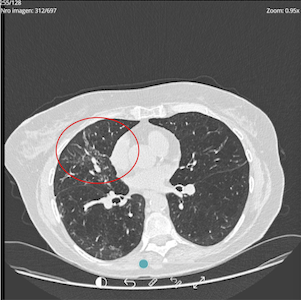

Response to treatment may also be reflected in improvement in complementary studies.

PRE-TREATMENT

OCTOBER 2024

POST-TREATMENT

SEPTEMBER 2025